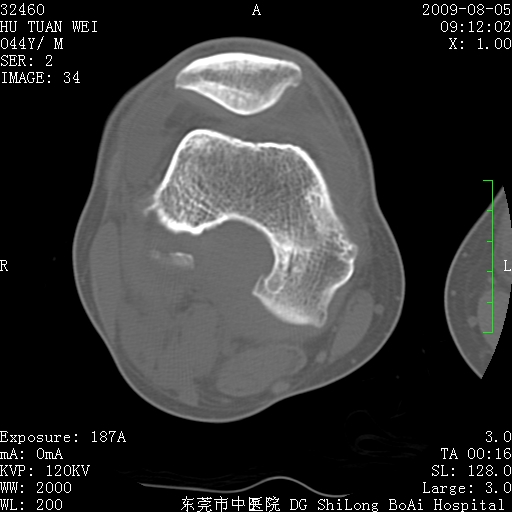

中年男性,膝韧带损伤术前检查!其他病史不清粗,不是我接手病人、且出院了!

1、股骨下段囊状膨胀性病变,边缘硬化明显,内多个残留骨棘呈多房型改变,囊腔密度较高无钙化,膝关节滑膜囊增厚,密度增高,关节腔少量积液。考虑:邻关节囊肿、退变性囊肿(软骨下囊肿)、着色性绒毛结节性滑膜炎、abc、骨巨、良性纤维组织细胞瘤等鉴。虽然年龄偏大,部位于骨端,但有外伤史,本人还是倾向于动脉瘤样骨囊肿(abc)可能性大。邻关节囊肿及软骨下囊肿次之考虑。

2、胫骨髁间棘撕脱骨折,交叉韧带损伤可能;

3、关节退行性改变。

病理结果:色素沉着绒毛结节性滑膜炎

感谢反馈病理结果!本病为慢性关节病变。以关节滑膜高度增生、绒毛结节形成伴含铁血黄素趁着为特点。病因:有炎症、肿瘤、外伤关节出血、代谢障碍、变态反应及感染等学说。增强扫描呈关节腔内单个或多个强化的软组织结节影或滑膜不规则增厚伴关节积液为本病的特征性表现。